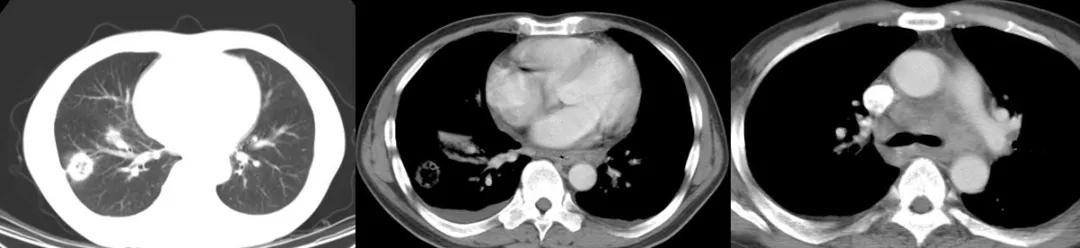

对于ICH的肺结核病影像表现,我与大家分享一些病例

病例1:

68岁,男性,2017年1月入院。主诉:反复发热2月,右侧胸隐痛;现病史:胸部CT示双肺散在炎症,抗感染治疗(头孢菌素、呼吸喹诺酮)后有吸收;但症状反复。

寻常型天疱疮,长期美卓乐、硫唑嘌呤治疗;类固醇性糖尿病。

CRP 196↑ mg/L;白细胞计数 9.12 ×10^9/L 中性粒细胞% 98.2;反复痰找抗酸杆菌(-)。

右侧胸腔穿刺,抽得脓性胸水,胸水涂片见抗酸杆菌4+。

图:2017-1 胸部CT:左肺上叶后段团片影,较前片有所减小;两肺多发炎症,较前片部分吸收;右侧胸膜增厚、胸腔积液,较前片有所增多。

病例2:

男性,42岁。 2008年诊断干燥综合症,当时胸部影像学未见异常。糖皮质激素30毫克/日 ,减量过程中口干症状加重,2009年7月再次全身检查,胸部CT见左上肺尖段软组织影,伴空腔。(似乎存在空洞,有些低密度区,但究竟是不是空洞呢?需要进一步确认。)

病灶穿刺病理:肉芽肿性炎伴坏死,抗酸染色+。

抗痨治疗6月后:

病例3 :

男,50岁,发热1月;骨穿:感染象;胸部CT:右肺阴影,纵膈淋巴结肿大。

这位患者入院时,完全像是白血病化疗过程中出现的改变,那么,会不会是白血病的肺部浸润呢?但是白血病肺部浸润较多见间质的浸润,而这位患者病变呈片状,是实质性的浸润……我们给患者做了骨穿,证实是感染象。

最终痰抗酸染色阳性、血HIV阳性;患者为同性恋。

病例4:

男性,26岁。2015年8月入院,因「咳嗽、咳痰一个半月,胸痛半月,加重伴高热一天」入院。 糖尿病病史8年余,平素血糖控制差,入院时尿酮体+++。

图:胸部CT:右侧液气胸,右肺实变,伴空洞及气液平。

病例5:

男,52岁,溶血性贫血,激素治疗43天。

最初完全按照大叶型肺炎、细菌性肺炎治疗,没有明显效果。最后出现播散,用了机械通气,出现气胸等等。

病例6:

这位患者是急性单核细胞性白血病,化疗2个疗程后出现病症——发热、咳嗽,咳黄痰,很多人会因此想到细菌性肺炎。但事实上,做了气管镜、采样、活检,证实有大量的抗酸杆菌。肺组织活检证实是肉芽肿改变,最后确诊肺结核。

经过治疗以后明显吸收好转:

病例7:

患者是混合性结缔组织疾病,激素治疗6个月后出现发热,肺部病灶明显增多,两侧情况不一样,我们冒了很大风险给他做支气管肺泡灌洗,做刷检、做活检,刷检时也找到了抗酸杆菌,但活检的结果是:既有一般的结缔组织的肉芽肿性改变,同时也看到有结核的干酪样坏死。因为患者是在激素减量过程中出现的症状,所以我们考虑是既有结缔组织疾病,又合并了肺结核。